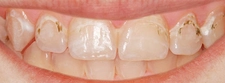

Riskleri Minimize Etme Yöntemleri

1. Uzman Seçimi: Diş ekimi yapacak olan doktorun deneyimi ve uzmanlığı, işlemin güvenliği açısından kritik öneme sahiptir. Güvenilir bir hekim seçmek, komplikasyon riskini azaltır.

2. Steril Ortam: İşlem sırasında kullanılan aletlerin ve ortamın steril olmasına dikkat edilmelidir.

3. Hastanın Genel Sağlık Durumu: İşlem öncesi genel sağlık kontrolü yapmak, mevcut sağlık sorunlarının tespit edilmesine ve buna göre önlem alınmasına yardımcı olur.

4. İlaç Kullanımı: Doktorun önerdiği antibiyotik ve ağrı kesicilerin düzenli kullanımı enfeksiyon riskini azaltabilir.